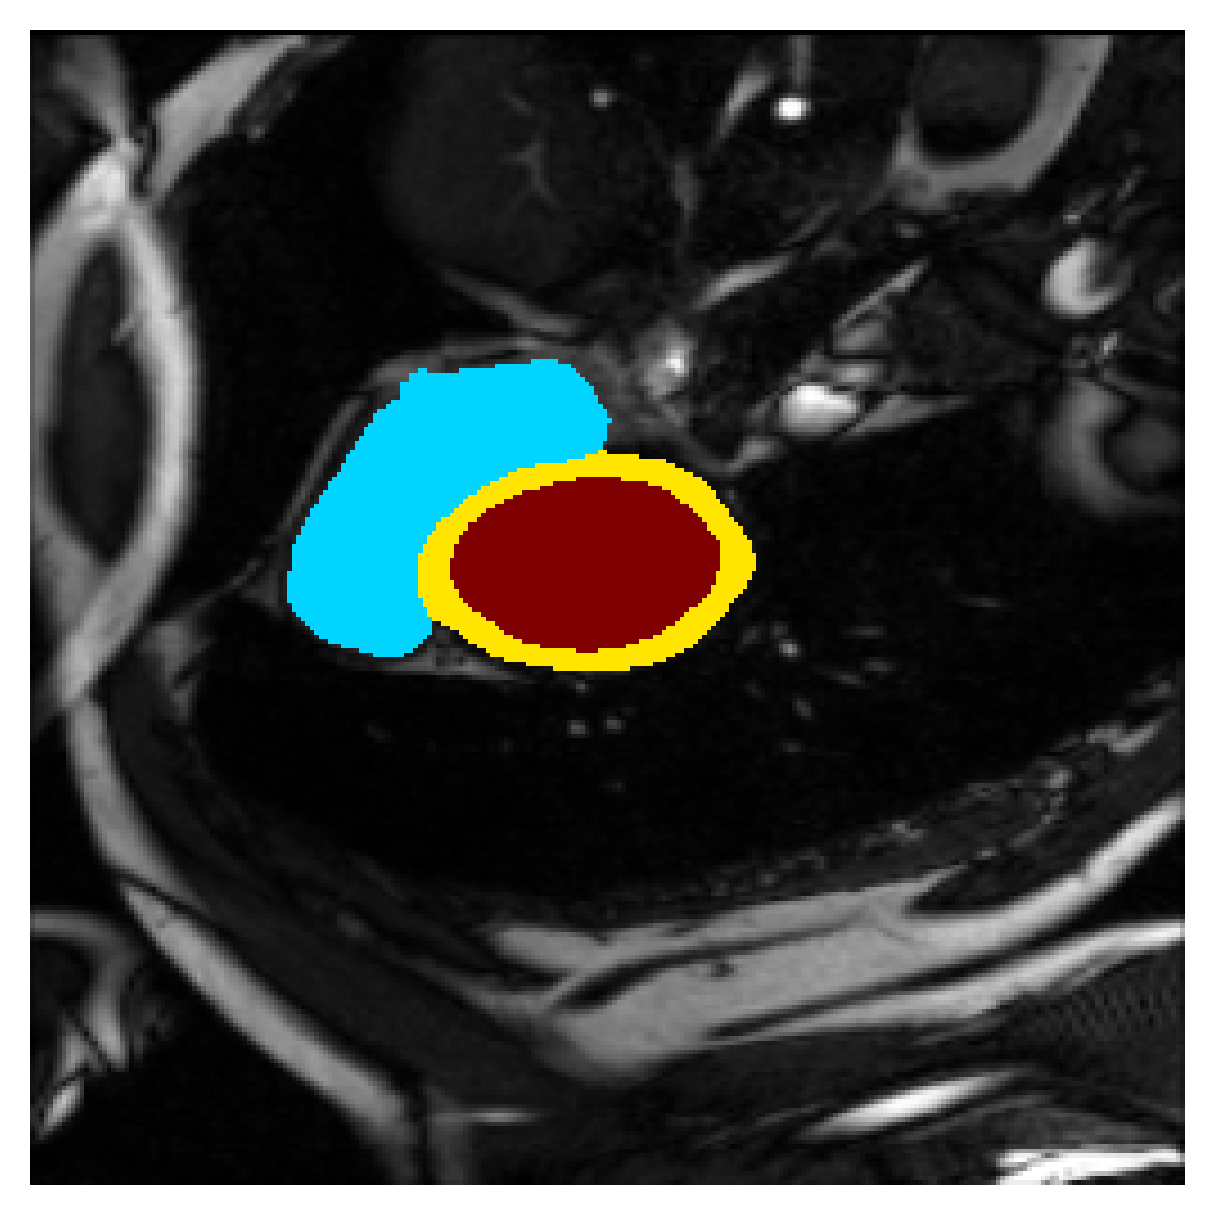

5.1 Segmentation of cardiac structures

The average 3D Dice scores and HD95 values on the ACDC test set are given in Table 2, and boxplots in figures 4 and 5 show the distributions. We see that, in terms of DSC, the proposed strategy of using intensity-aware distances withing boundary loss performs better than simply using the Euclidean distance, with the best results achieved by using the strictly intensity based MBD. The HD95 however favors the original version of , which may be do to its smoother predictions and less fragmentation and oversegmentation. The CRF-loss results are significantly worse in both metrics.

In Figure 3 we show the 3D DSC validation curve evolution for a single run. The CRF-loss seems to have converged to a low DSC value, while all settings combining CE and boundary loss reach values close to the full supervision in the beginning of the training and then slowly collapse towards to the point annotations. The MBD version stands out, degrading slower, thus providing a wider range of potentially good models for evaluation.

Qualitative comparison

In Figure 6 we provide qualitative results on a number of randomly chosen test set slices. Upon visual inspection, we can observe that training with the intensity-aware distances (particularly with and ) follows the image gradients better and is better at recovering the underlying shape than the Euclidean version. The CRF-loss seems to recover the shape of the myocardium and left ventricle to some extent, but fails entirely on the right ventricle.